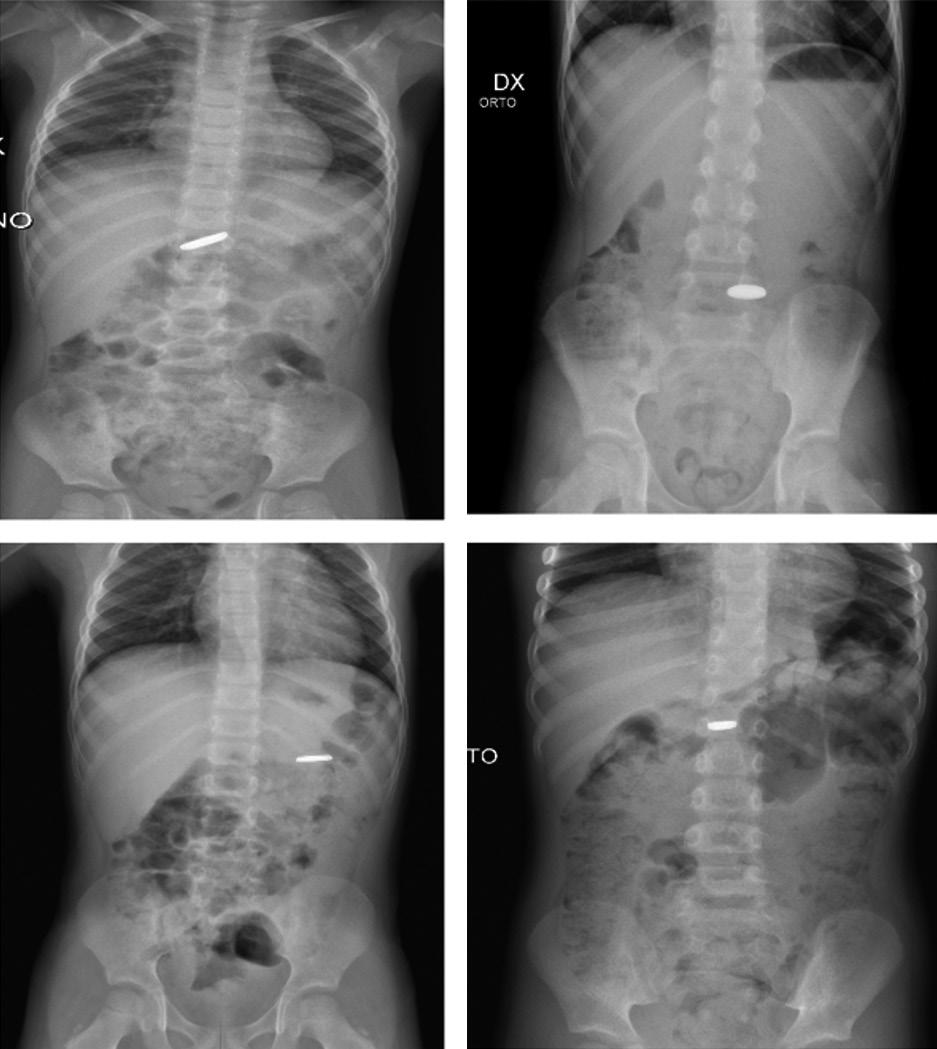

1 UO di Pediatria, Ospedale G.B. Morgagni – L. Pierantoni, AUSL della Romagna, Forlì; 2 Scuola di Specializzazione in Pediatria, Università degli Studi di Ferrara

La piomiosite – inizialmente conosciuta come patologia prevalentemente tropicale e oggi ben presente anche nelle zone temperate – è un’infezione suppurativa del muscolo scheletrico che può originare da un traumatismo o da un’intensa attività fisica che determina un danno della struttura muscolare. Spesso sostenuta da Staphylococcus aureus , entra in diagnosi differenziale con l’artrite settica, l’osteomielite e la cellulite. La descrizione di un caso osservato in un giovane atleta ci consente di ripercorrerne gli elementi diagnostici e terapeutici fondamentali.

Pyomyositis – initially known as a predominantly tropical disease and now well present also in temperate areas –is a suppurative infection of the skeletal muscle that can originate from trauma or intense physical activity that causes damage to the muscle structure. Often sustained by Staphylococcus aureus , it enters a differential diagnosis with septic arthritis, osteomyelitis and cellulitis. The description of a case observed in a young athlete allows us to retrace the fundamental diagnostic and therapeutic elements.

La storia di Sergio Sergio, ciclista dilettante di 11 anni, viene in pronto soccorso per la comparsa di dolore elettivo a livello della cresta iliaca di destra da circa quattro giorni, associato a zoppia e febbre (TC max 38,5 °C) da un giorno, scarsamente responsiva agli anti piretici. Riferisce inoltre alcuni episodi di vomito alimenta re. Non riporta di avere subito traumi significativi. Il ragazzo è, complessivamente, in buone condizioni generali e a carico dell’articolazione coxo-femorale di destra non ci sono segni di infiammazione locale né limitazione ai movimenti di intra- ed extrarotazione. Lamenta dolore solo alla digitopressione del la regione antero-superiore della cresta iliaca di destra. La re stante obiettività è nei limiti della norma. Tra gli esami, emo cromo, funzionalità epatica e renale sono nella norma con un incremento della PCR (58,1 mg/L) e negatività della sierolo gia per parvovirus B19, CMV, EBV, micoplasma, bartonella e Widal-Wright. Anche la radiografia del bacino non evidenzia lesioni ossee.

Nell’ipotesi di un’osteomielite acuta si avvia trattamento con oxacillina per via endovenosa. Dopo 72 ore di terapia antibio tica, persistendo la febbre e pervenuta la positività dell’emo coltura per Staphylococcus aureus multisensibile, si sostitui sce la terapia in atto con la clindamicina per via endovenosa. In quarta giornata di ricovero la RM del bacino mostra estesi fenomeni di infiltrazione edematoso-flogistica con alcuni fo colai ascessuali che interessano soprattutto il muscolo medio gluteo e in minor misura l’ala iliaca destra [Figura 1]. Il qua dro è complessivamente suggestivo di piomiosite con inizia le coinvolgimento del periostio e dell’osso. Durante la degen

Figura 1. RM all’esordio che mostra l’interessamento infiammatorio del muscolo medio gluteo e dell’ala iliaca destra.

za Sergio migliora progressivamente riuscendo a deambulare seppure con gli ausili e resta apiretico dalla sesta giornata di trattamento. Dopo 16 giorni complessivi di terapia antibiotica endovenosa, gli esami mostrano la completa negatività degli indici di flogosi, l’ecografia muscolare rileva un’apprezzabile riduzione dell’area di infarcimento edematoso-flogistico sen za più evidenza dei focolai ascessuali. Il ragazzo viene dimesso con indicazione a proseguire la terapia con clindamicina per via orale per un totale di 21 gg. La RM, eseguita a distanza di un mese dalla precedente, documenta un significativo miglio ramento del quadro flogistico-suppurativo a carico del mu scolo medio gluteo, rimanendo solo una circoscritta area di interessamento nelle porzioni più craniali in adiacenza dell’a la iliaca. La terapia antibiotica viene proseguita per altre tre settimane e l’ulteriore RM a due mesi dall’esordio conferma la pressoché totale risoluzione dell’interessamento muscolare e osseo [Figura 2].

Quello che c’è da sapere sulla piomiosite (PM) Inizialmente descritta, alla fine dell’Ottocento, come miosite tropicale perché particolarmente frequente (1-4% dei ricove ri ospedalieri) nelle regioni tropicali subsahariane e in Brasi le, Giappone e Uganda, la PM è una patologia che colpisce più frequentemente adolescenti e giovani adulti anche se può in sorgere in tutte le fasce di età, con una maggiore incidenza nel sesso maschile. La sua crescente diffusione, anche nelle regio